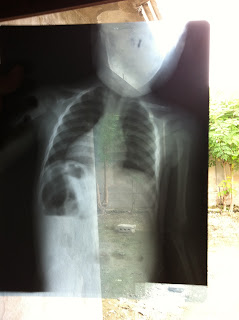

This is the xray from the little boy.

Plans for the children in Lilavois are still being discussed but were put on hold for a few days after we visited another children's home called Tree of Life in Bon Repos Latan yesterday. We dropped off silverware, plates, and towels and discovered some very sick children in doing so. The children were healthy the last time they were checked on which was about a week ago but once one child gets sick they all get sick. I could see just by looking at some of the children that they were malnourished and others very ill. One boy in particular was put in another room due to a recent respiratory infection. I went in, assessed him, and took a look at the medication he was getting. A doctor prescribed him oral suspension flagyl near the end of May. The staff also showed me an xray of the boys chest which really surprised me. I'm not too familiar with radiology but I tried to make an educated guess. I really wished my mom would have been there to decipher it more accurately for me. I took a photo of it which now makes it superimposed but I posted it below. Maybe my medical readers can help me diagnose it accurately. Anyway there were three bottles of flagyl, all halfway empty, and the boy still showed no signs of improving. I wonder a lot of things: Is he malnourished? Is he getting the medication he needs everyday? Was flagyl an accurate medication to prescribe him? It's such a challenge working in these environments without the resources I have in the United States. I expressed my frustration to a woman I had just met in Haiti last week, Jane, via email. She reminded me I am here to do God's work and that is always worth it and I need to know in the long run I did my best. Her words were comforting but I'm still struggling with it all. I'm slowly realizing how many issues are really going on in this country. I want to help everywhere but there is so, so much. Randy gave me good advice the other day; Look at the day and focus on what you can do today. Take things day by day.